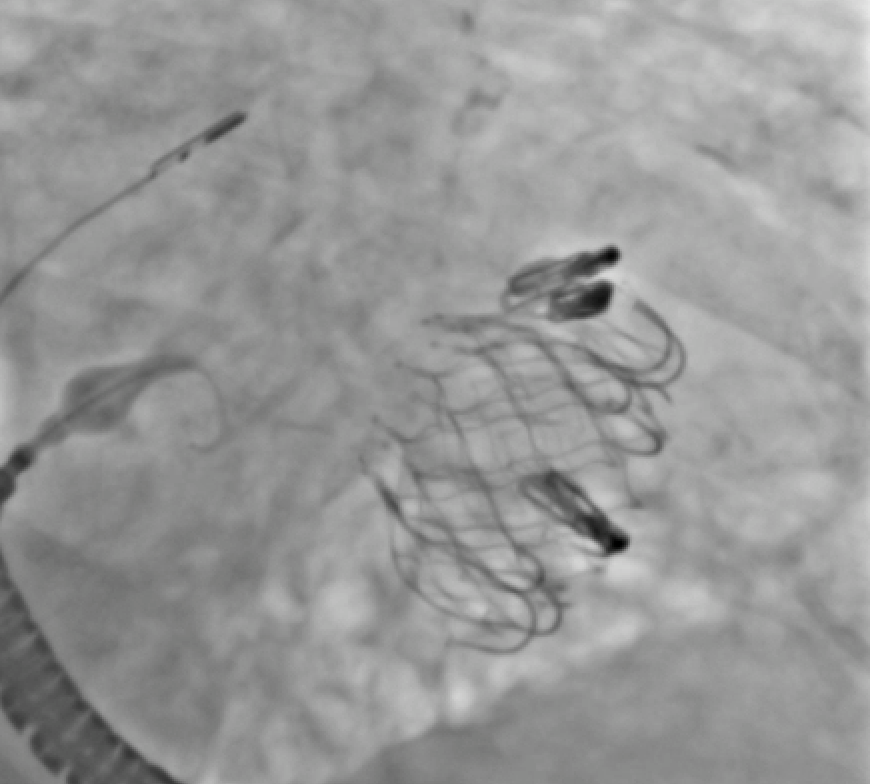

25 days

Just published: Beyond Limits in Alternative Access: The Success of Right Subclavian Transcatheter Mitral Valve Replacement https://t.co/tqabVP6z8e @Brianponeill @PedroMDMSc @engelpedro @GKFram @AhmadJabri8